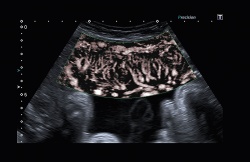

Jader Cruz MD, also agree with this. An obstetrician with the Centro Hospitalar in Lisbon and a leading authority in foetal medicine, Dr Cruz said that, with SMI, ‘We can see things we are not used to seeing. We’re learning how to look at the images, to interpret them and asking how we can apply these assessments in the future.’

In a unique application of Superb Microvascular Imaging, Dr Cruz examined the microcirculation in the tiny hearts of foetuses at 12 weeks and found the monochrome mode the most effective in this assessment. ‘While SMI was not developed for this exam, it works very well here because it removes the clutter in the ultrasound image,’ he explained. ‘You cannot see these hearts very well with 2-D ultrasound, but now, with SMI, I can see the structures very well – a view of the four chambers, the vessels, everything. I can see the chambers filling, even the crossing of the vessels. Most impressive for me is to see the septum, a clear view of the septum, and as I sweep down I can see the aorta coming out. This is amazing.’